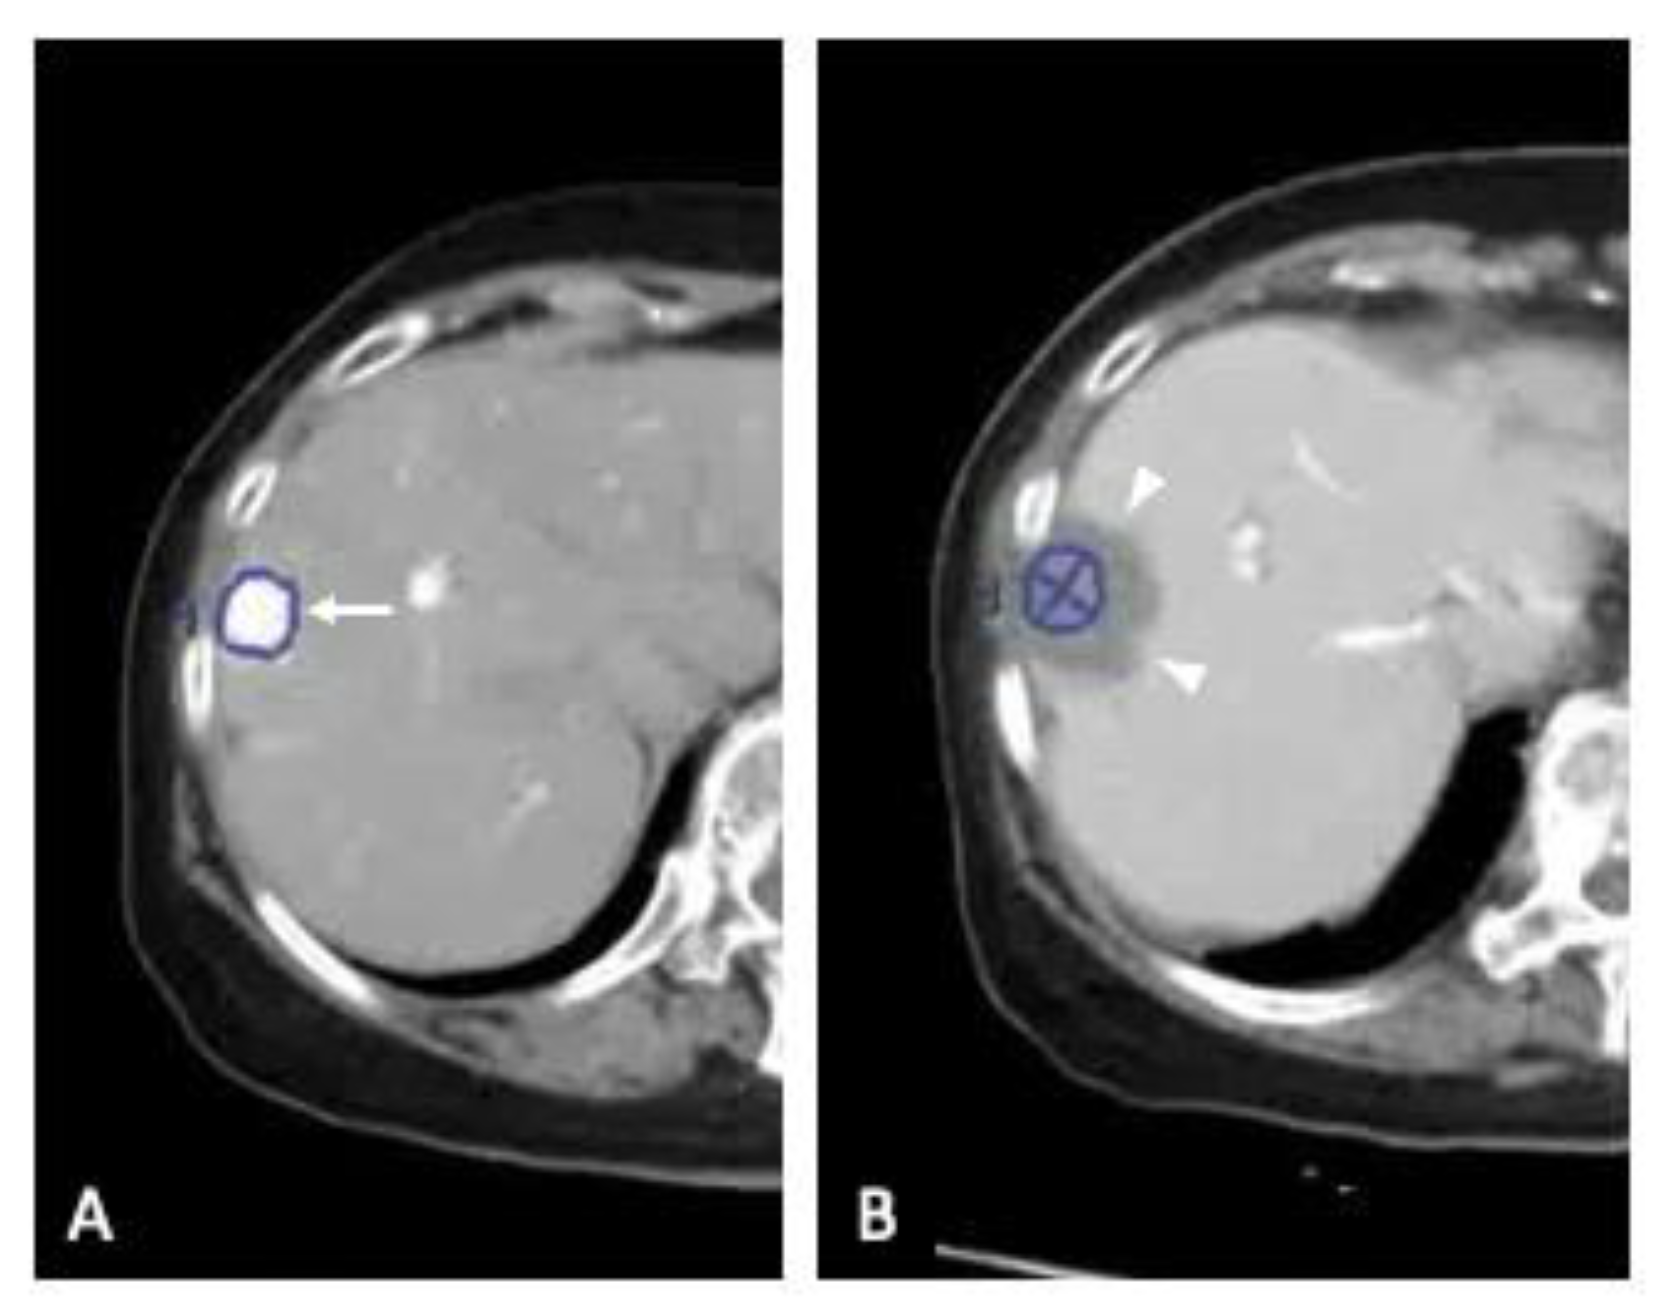

2.2. Three-Dimensional Assessment of Ablative Margins Using Overlay Fused CT/MRI Imaging